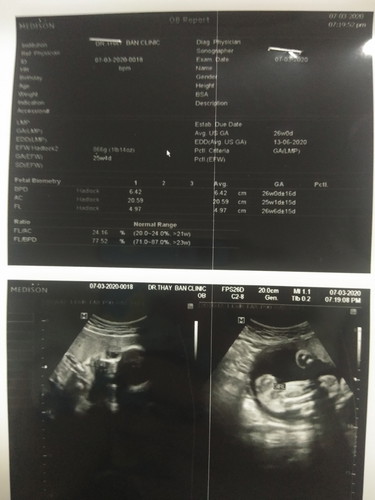

มาโชว์น้ำหนักลูกกับใบอัลตร้าซาวด์ลูกๆทีม มิ.ย 63 กันจ้า บ้านนี้กำหนดคลอด 10 มิ.ย 63 ได้ลูกสาว น้ำหนักลูก 866g จ้าดิ้นเก่งมาก?? แม่ๆบ้านอื่นล่ะค่ะถึงไหนกันแล้ว

ทีม มิย. 63 ลูกน้ำหนักถึงไหนกันแล้วค่ะ ได้กี่วิคกันแล้ว บ้านนี้ 25w 866g??